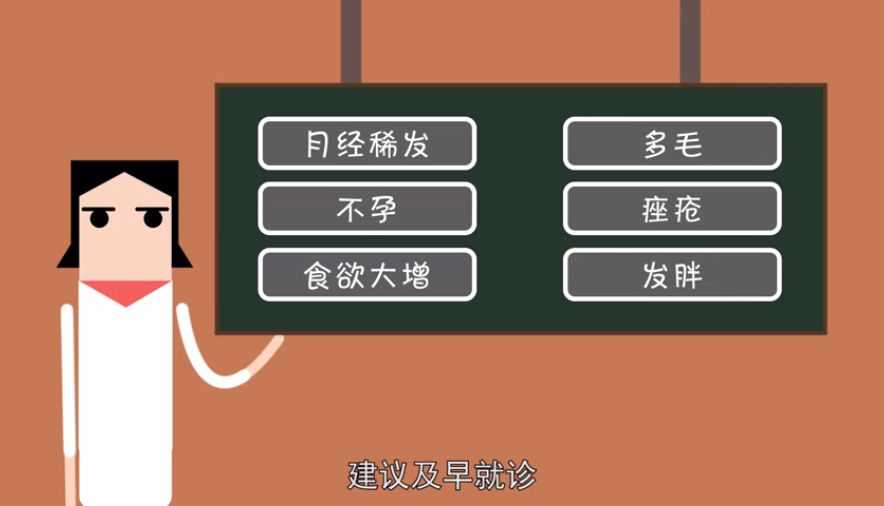

Q5备孕检查时发现多囊卵巢综合征、腺肌症、子宫肌瘤等,这些问题会对怀孕产生影响吗?

这些问题在育龄妇女中是很常见的,比如说多囊卵巢综合征,如果患者月经出现了问题,就说明她排卵也有问题,这一部分人想要怀孕的话必须找医生。

Q7举例来说,多囊卵巢综合征的患者该如何备孕呢?

有的多囊卵巢综合征患者来到医院后会说,我结婚了多少年但是一直没怀孕,现在月经也不好。之后通过化验和辅助检查,我们医生才能判断这个患者有多囊卵巢综合征。

其实多囊卵巢患者是没有成熟卵的,是不会怀孕的,经过医生的调整、治疗后才能怀孕,这样的案例我们也有很多。还有一部分多囊卵巢患者是偶发地排卵导致怀孕的,但是由于她的基础状态没有调整好,在怀孕的过程中可能会流血,甚至流产。

尤其是对于胖型的多囊卵巢综合征患者,我们医生希望她们在怀孕前最好来就医,让医生做一个生殖的评估和孕前的调整,把机体调整到最佳状态,这时怀孕才是最好的。

如果从临床上自身感觉来看,第一个表现就是月经紊乱,它会出现月经稀发、闭经,有些人还会出现围绝经期的表现,比如说盗汗、烦躁、易怒、面部皮肤衰老、生殖器官干涩等。